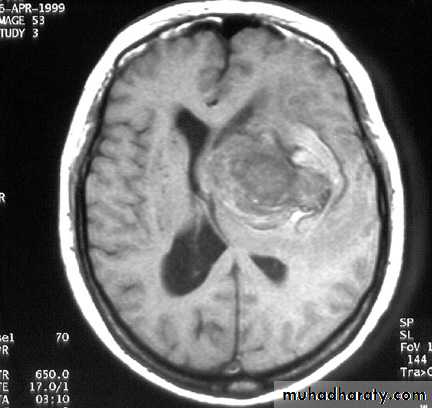

GLIOBLASTOMA MULTIFORMI

GM AXIAL MRI